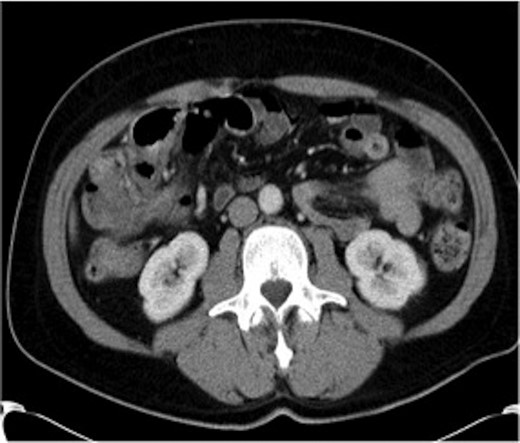

Haemoglobin was 14.9 g/dl and the white cell count (WCC) was 9 × 109/l. Other remarkable laboratory tests included a C-reactive protein (CRP) of 15 mg/l. Urinalysis was normal. The plain X-ray abdomen (AXR) (Fig. 1) revealed dilatation of a focal segment of large bowel with mildly dilated small bowel. Computed tomography (CT scan) of his abdomen reported that the gas-filled viscus is likely to represent the caecum (Fig. 2).

CT of the abdomen (Case 1) demonstrating the gas-filled caecum.

A presumptive diagnosis of caecal volvulus was made and the patient was taken to theatre. Laparotomy revealed an omental band wrapping the colon at the junction between the caecum and the ascending colon with a marked dilatation of the caecum. The caecum was viable and the appendix was normal. The rest of the large bowel and small bowel were normal. The band was dissected free off the colon and excised. Appendicectomy was performed and the gas in the caecum was aspirated via the appendicular stump prior to its ligation.